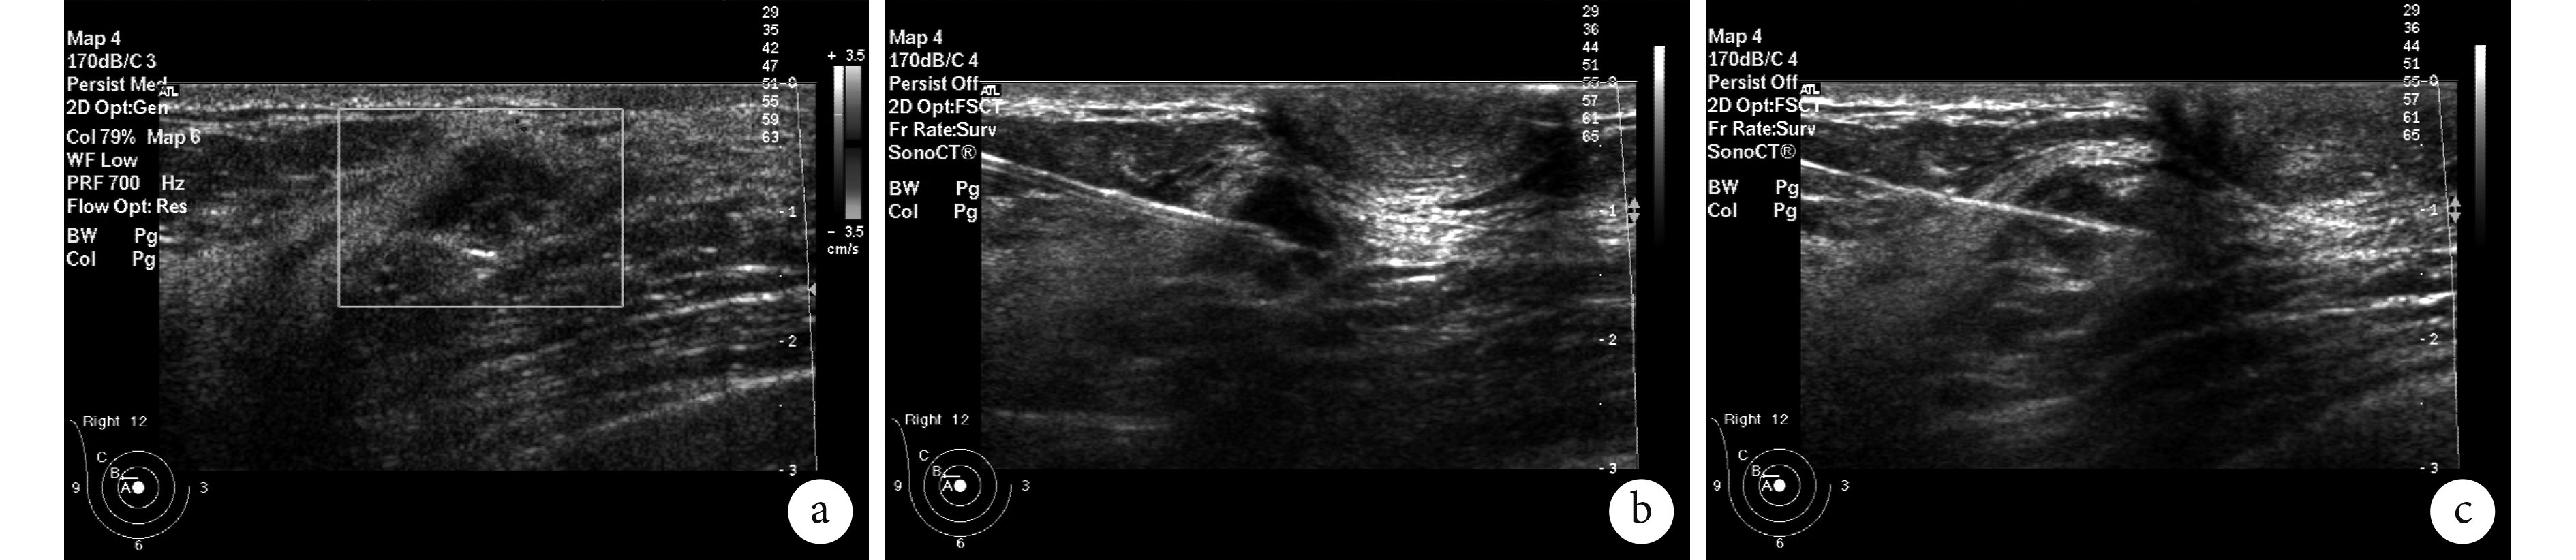

1.2.4 導絲置入定位技術的操作流程 患者取仰臥位,腫塊位于乳腺外側時可半側臥位。雙手自然上舉,置于兩耳外側,充分暴露定位側的乳腺。第 1 步,超聲介入醫師進行超聲復查,確定需要導絲置入定位的腫塊位置和大小與外科醫師醫囑要求定位的腫塊一致,不一致者需告知患者及其家屬,并與外科手術醫師溝通,達成一致意見后方可實施。第 2 步,十字交叉法確定腫塊中心位置,并做好其體表標記,然后常規消毒鋪巾,探頭表面涂無菌耦合劑后用無菌套包裹,首選短軸法進針,保證探頭中心點深面為腫塊中心點,先以 2%利多卡因局部浸潤麻醉,然后從探頭中心點位置進定位針,進針過程中采用提插法以顯示針尖位置,進針直至針尖進入腫塊深面 3~5 mm時退出針鞘,退出針鞘時需固定導絲,退出針鞘后輕輕拽拉和抖動導絲,超聲下可見腫塊隨之輕微移動,表明鉤針定位成功。導絲的尾端打圈,醫用紗布覆蓋,膠布固定紗布后患者步行回病房。對于腺體較薄的女性,腫塊深面通常沒有足夠的腺體或脂肪組織,可在退出針鞘前將針鞘打斜,這樣探頭可顯示穿刺針鞘的長軸和針尖位置,針尖穿過腫塊 3~5 mm退出針鞘,導絲處理同前。對于新開展導絲置入技術的超聲介入醫師,短軸法難度相對較大,可改為長軸法穿刺,但進針點盡量臨近腫塊,這樣的操作過程,探頭可清楚顯示針尖和針體及其前進方向,有利于新手對導絲置入技術的把控。穿刺過程可使用消毒耦合劑或碘伏顯示針尖和針體(圖 1)。報告應清楚地說明導絲置入腫塊的具體位置,置入腫塊內外上下的哪一側、邊緣還是中央,供外科醫師參考,有利于腫塊被完整切除。